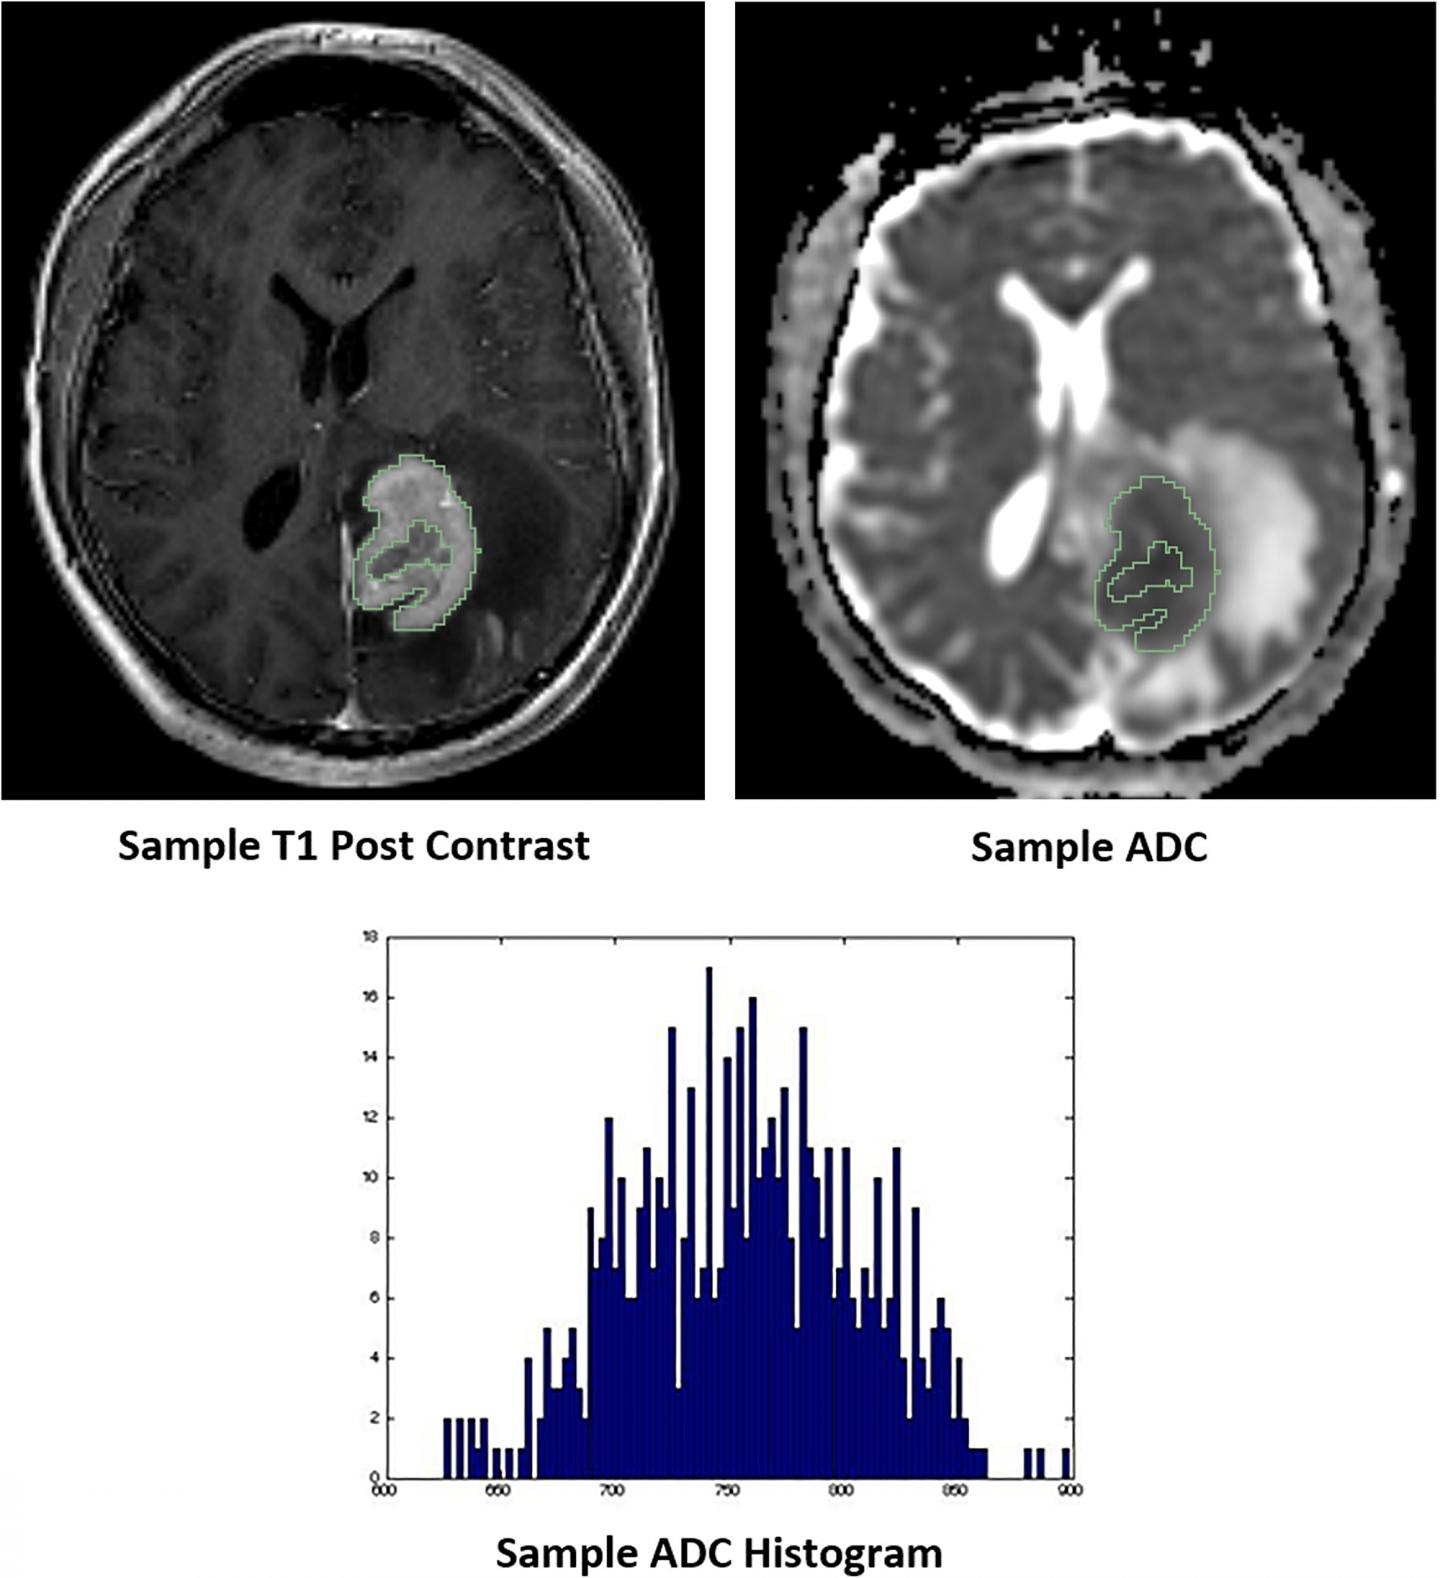

image: Representative images of whole tumor volume segmentation of the co-registered T1 post-contrast sequence and apparent diffusion coefficient (ADC) map, yielding the corresponding ADC histogram distribution utilized for data analysis.

The cover for issue 45 of Oncotarget features Figure 3, "Representative images of whole tumor volume segmentation of the co-registered T1 post-contrast sequence and apparent diffusion coefficient (ADC) map, yielding the corresponding ADC histogram distribution utilized for data analysis," recently published in "Diffusion-weighted MR imaging histogram analysis in HIV positive and negative patients with primary central nervous system lymphoma as a predictor of outcome and tumor proliferation" by Khan, et al.

Diffusion weighted imaging and corresponding apparent diffusion coefficient maps can provide a representation of the cellular microenvironment with several studies demonstrating that ADC values can predict tumor cellularity across various neoplasms, including lymphomas.

However, tumor segmentation was performed using only the ADC sequence with the potential inclusion of intra-tumoral necrosis, hemorrhage or regions outside of the actual solid tumor that would otherwise have been excluded with contrast co-registration, ultimately providing a suboptimal representation of true tumor parenchyma.

The primary aim of this study is to more comprehensively evaluate the relationship between ADC calculations with tumor Ki-67 expression and clinical outcomes using a larger patient sample with the inclusion of PLWH and whole tumor segmentation with T1 post contrast co-registration.